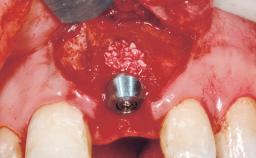

Immediate Flapless Placement of an Implant in a Maxillary Left Central Incisor Site

A 29-year-old female patient presented for treatment to replace the upper left central incisor tooth with an implant- supported restoration. The tooth had been intermittently symptomatic for the previous 12 months. The tooth had originally suffered trauma about 15 years previously. Several endodontic treatments had been performed, including an apicectomy procedure to retain the tooth. The patient was healthy and a non-smoker. She had reasonable expectations in regard to esthetic outcomes and the risk of marginal tissue recession following treatment. At medium smile, the gingival margins of the upper teeth were visible, with a display of 3 to 4 mm of the gingival margins. Gingival recession of tooth 21 and a discrepancy in the gingival levels between teeth 11 and 21 was observable during normal speech and smile.